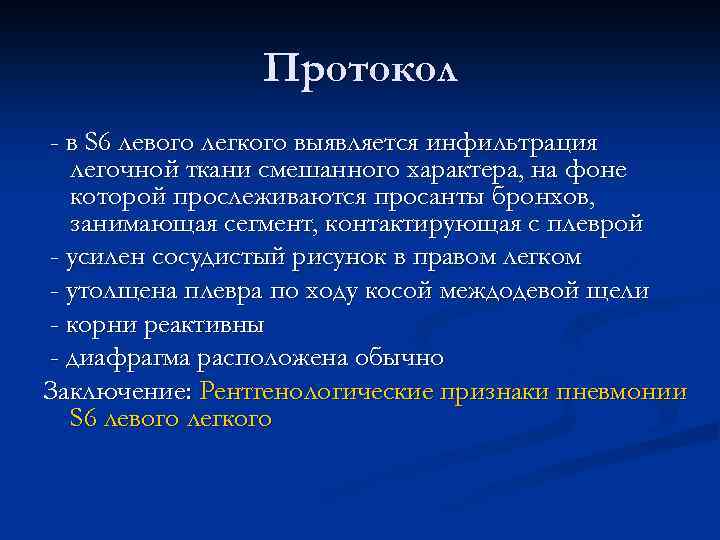

Пневмония S 6 левого легкого

Протокол - в S 6 левого легкого выявляется инфильтрация легочной ткани смешанного характера, на фоне которой прослеживаются просанты бронхов, занимающая сегмент, контактирующая с плеврой - усилен сосудистый рисунок в правом легком - утолщена плевра по ходу косой междодевой щели - корни реактивны - диафрагма расположена обычно Заключение: Рентгенологические признаки пневмонии S 6 левого легкого